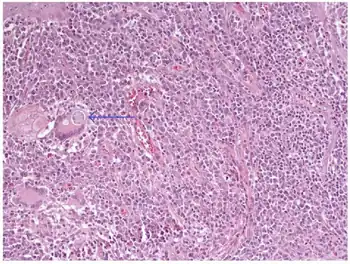

C. immitis can cause a disease called coccidioidomycosis (valley fever).[10][11][12] Its incubation period varies from 7 to 21 days.[13] Coccidioidomycosis is not easily diagnosed on the basis of vital signs and symptoms, which are usually vague and nonspecific. Even a chest X-ray or CT scan cannot reliably distinguish it from other lung diseases, including lung cancer. Blood or urine tests are administered, which aim to discover Coccidioides antigens. However, because the Coccidioides creates a mass that can mimic a lung tumor, the correct diagnosis may require a tissue sample (biopsy). A Gomori methenamine silver stain can then confirm the presence of the Coccidioides organism's characteristic spherules within the tissue. The C. immitis fungus can be cultured from a patient sample, but the culture can take weeks to grow and requires special precautions on a part of the laboratory staff while handling it (screw cap vials and sterile transfer hoods are recommended).[14] It is reported as the tenth-most often acquired infection in the laboratory conditions with two documented deaths.[2] Until October 2012, C. immitis had been listed as a select agent by both the U.S. Department of Health and Human Services and the U.S. Department of Agriculture, and was considered a biosafety level 3 pathogen.